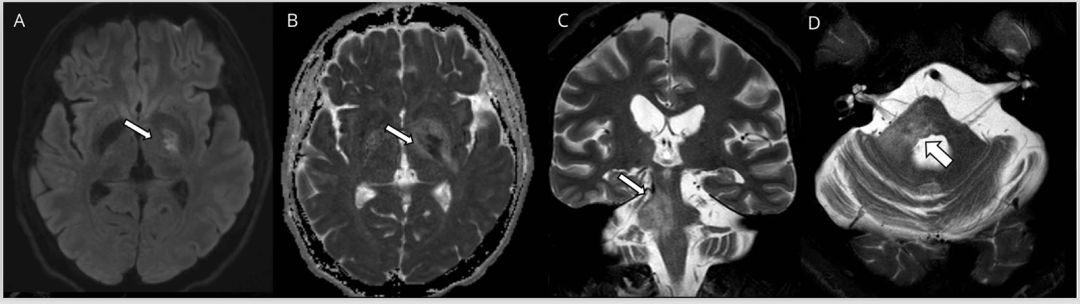

多发性硬化(MS)是中枢神经系统的获得性炎性脱髓鞘疾病,在MRI上病灶通常为卵圆形且界限清晰,T2和FLAIR序列呈高信号改变(图1)。在慢性病变过程中当轴突受损时,T1序列上可见低信号的黑洞征,但急性期也可能见到。新发病灶在3天到3个月内(平均3周)可见强化。虽然MS病灶会出现弥散受限,但当弥散发生变化时,弥散率通常会增加。当存在弥散受限时,特别是多发病灶和不在典型部位时,应考虑其他病因,例如SS或血管炎。

图1多发性硬化症患者的MRI影像。 轴位T2加权(A,B)显示脑桥外围界限清楚的卵圆形病灶(箭头)。 矢状位FLAIR图像(C,D)显示胼胝体下表面的病灶(C)和垂直于胼胝体的病灶(Dawson指征)(D)。